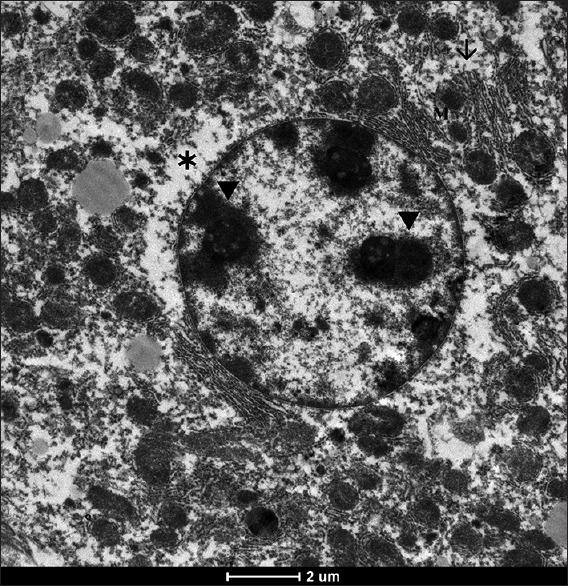

Ultrastructural Alterations of Liver Tissue Cells in Methotrexate-Treated Balb/c Mice.

Ultrastructural changes in rat livers perfused in vitro and in vivo with a high dose of methotrexate.

Hepatic ultrastructure in leukemic children treated with methotrexate and 6-mercaptopurine.

Cytoprotective effects of molsidomine against methotrexate-induced hepatotoxicity: an experimental rat study.